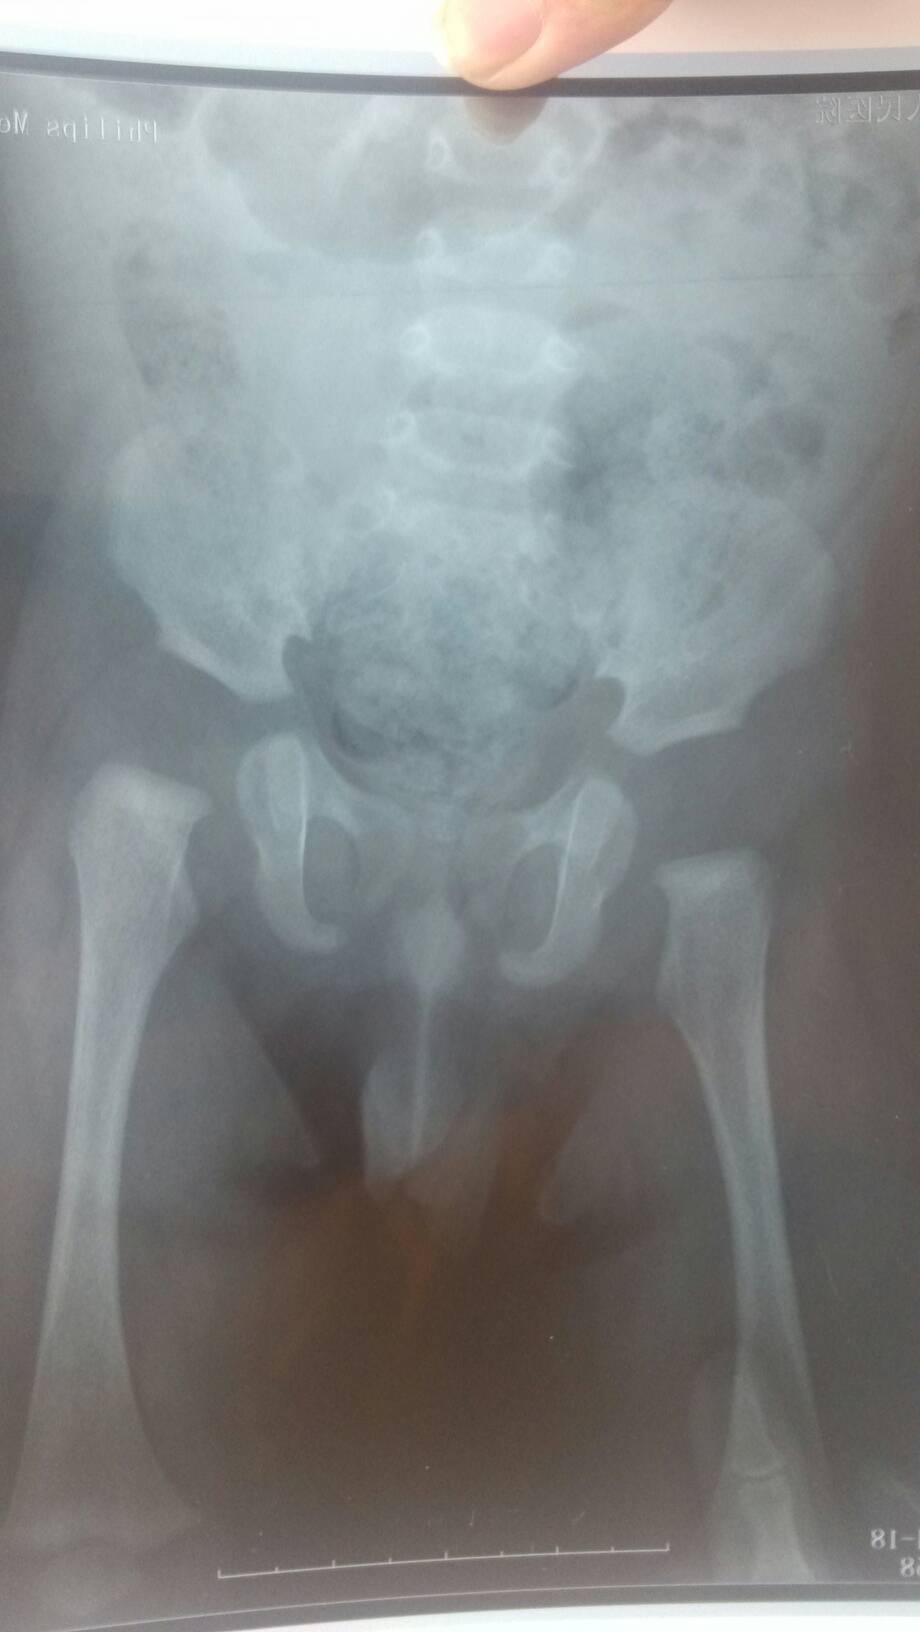

是胯骨脱臼吗,宝宝6个月 点击展开 匿名用户 2014-04-21 11:03 为您推荐: 其他回答 病情分析: 属于左侧髋关节脱位。 指导意见: 应该给予及时的髋关节复位治疗,如果为先天性的,可以采取手术矫正治疗。 匿名用户 2014-04-21 12:34 相关问题 为什么胯骨总是脱臼是什么原因呢 高龄产妇顺产导致胯骨脱臼怎么办呢? 高龄产妇顺产导致胯骨脱臼怎么办呢?